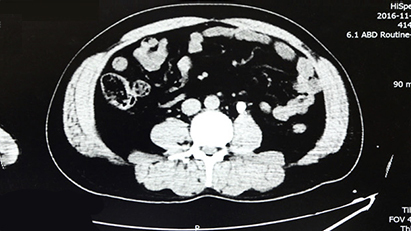

03CT 검사는 조영제를 쓸 수 없는 경우 CT 촬영을 통해 혈뇨를 진단합니다.

조영제를 쓸 수 없는 경우 CT촬영을 통해 혈뇨를 진단합니다.

02경정맥 조영술 및 초음파 검사, 컴퓨터 단층 촬영(CT)